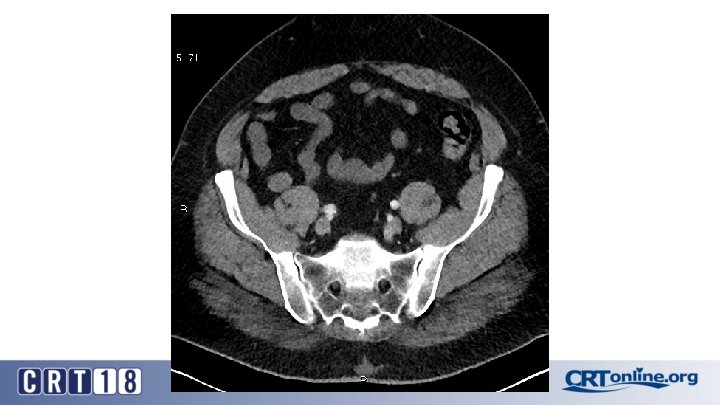

Blue Toe Syndrome

Returns Next day

Failed recanalization: BKA